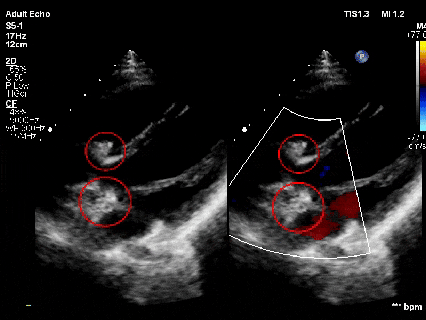

心脏超声:室间隔缺损(膜周部)、房间隔缺损(继发孔型)

术前TTE示:膜周部室间隔缺损,基底大小11.3×10.5mm,分流口大小3.6mm,左向右分流,峰值流速4.07m/s。

术前TTE示:房间隔缺损继发孔型,断端大小4.5-5mm,薄弱范围约10mm,左向右分流 。

释放前超声

释放前超声下封堵器型态良好,骑跨室间隔两侧

释放后超声

超声下可见室水平和房水平都无残余分流

心脏彩超:心脏超声下可见两个封堵器双盘稳固夹持,无残余分流;

术后1个月心脏超声,房室水平皆无残余分流